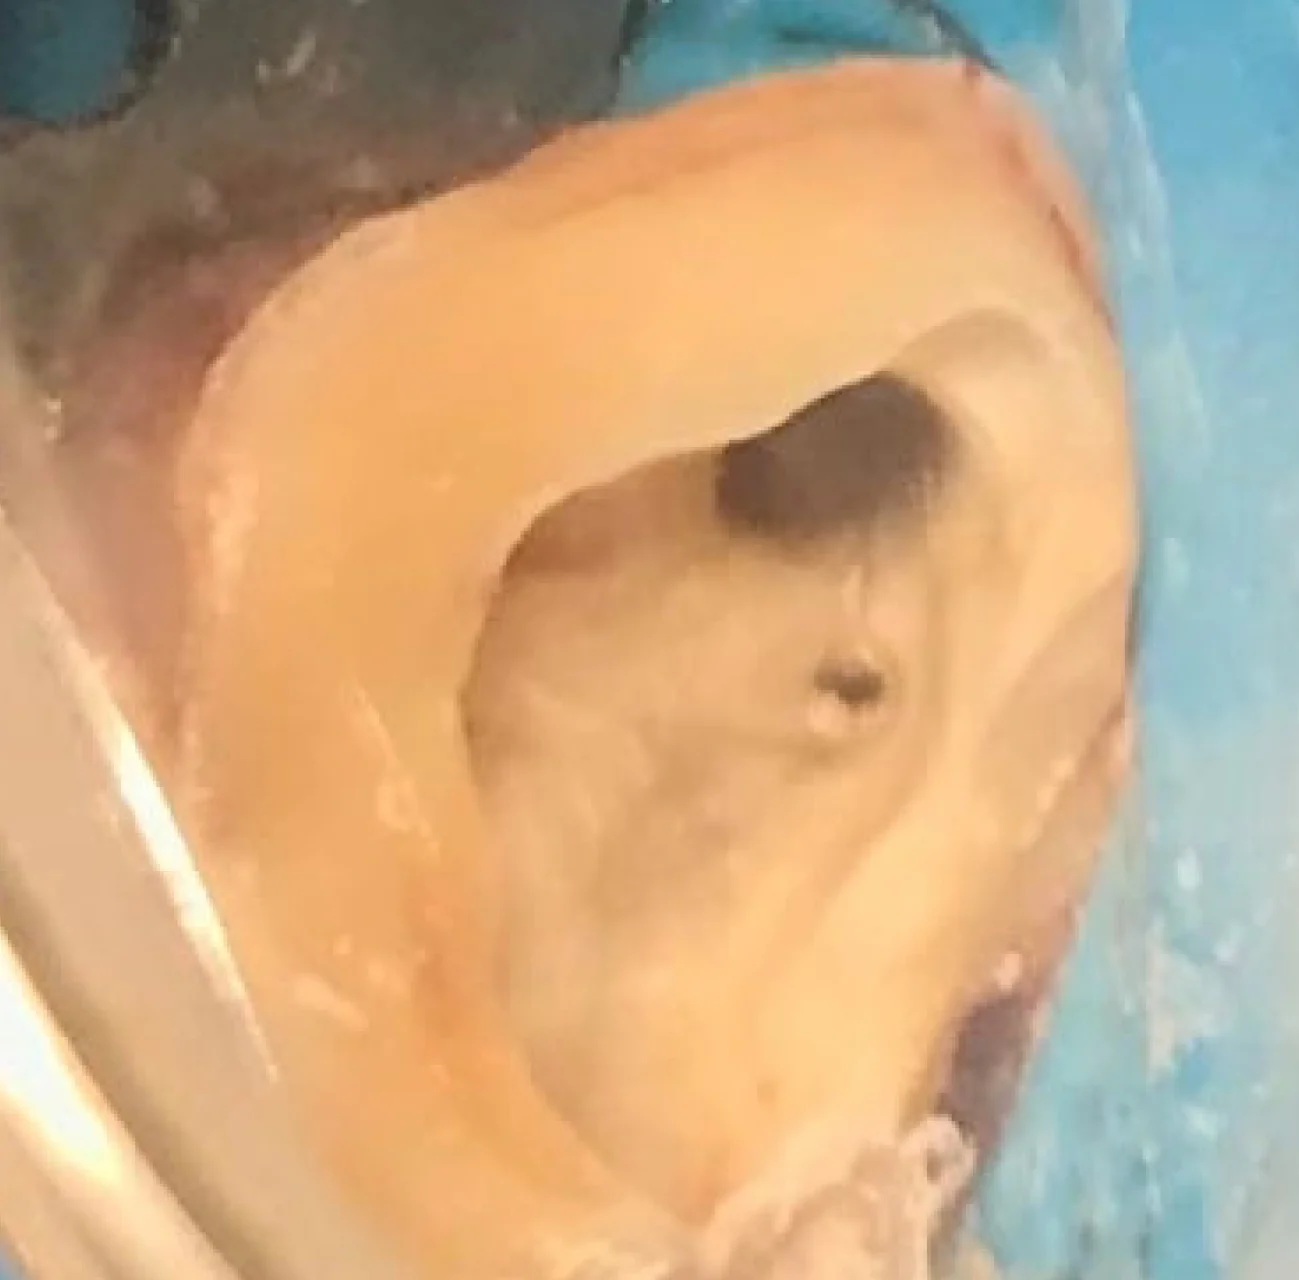

Vídeo de uma visão Microscópica

Auxílio no Diagnóstico

Visão Clínica

Visão Microscópica da fratura